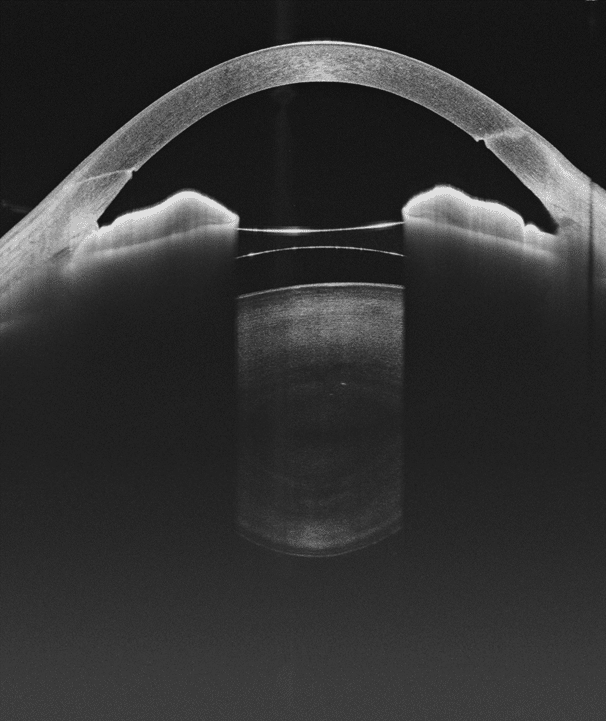

- HD Anterior Scan with Anterior OCTA

- 15mm Scan depth anterior